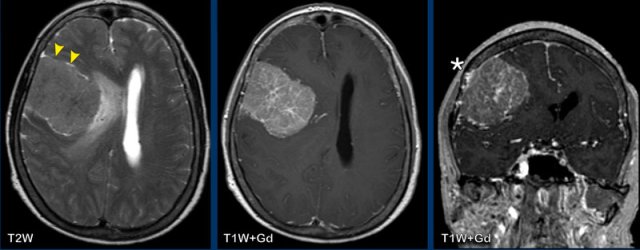

Meningioma

Findings:

- The tumor is extra-axial as can be seen on the T2W-image. There is CSF between the tumor and the brain parenchyma, this is called a CSF-cleft

- On T2W image the tumor has a relative low signal intensity

- There is homogeneous enhancement.

- Dural tail (arrowheads)

- Hyperostosis of the skull (asterix).

The images show a more aggressive looking lesion with edema

and midline shift.

Which findings favor the diagnosis of a

meningioma?

- The tumor has a flat dural base.

- Most important finding is the CSF between the tumor and the surrounding brain tissue (arrow heads). This finding definitely makes this an extra-axial tumor.

- Low signal on T2W

- Reactive changes in the skull (asterix) There is osseous involvement of the lesion. Not typical but frequently seen in a meningioma

The intraparenchymal

extension suggests a higher grade meningioma, while the presence of

edema is not a reliable sign of a higher grade.